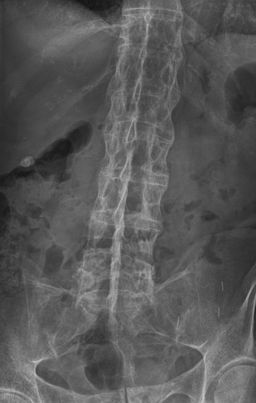

The vertebral bodies may become 'squared'. In later stages, bony bridges (syndesmophytes) form between adjacent vertebrae, there is ossification of spinal ligaments and, in late disease, there may be complete fusion of the vertebral column (bamboo spine).

Bamboo spine

© By Stevenfruitsmaak, via Wikimedia Commons